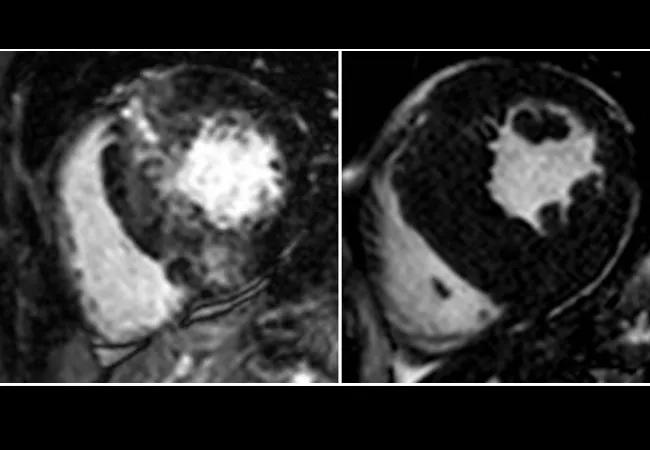

cardiac magnetic resonance images showing hypertrophic cardiomyopathy

CMR is emerging as a powerful tool for diagnosis and risk stratification in HCM, including assessment of left ventricular mass and pattern of hypertrophy. Late gadolinium enhancement by CMR is a marker of focal myocardial fibrosis, which is thought to underlie the arrhythmogenic substrate and promote development of heart failure.

Image at top: CMR images representative of those from participants in the HCM Registry study.